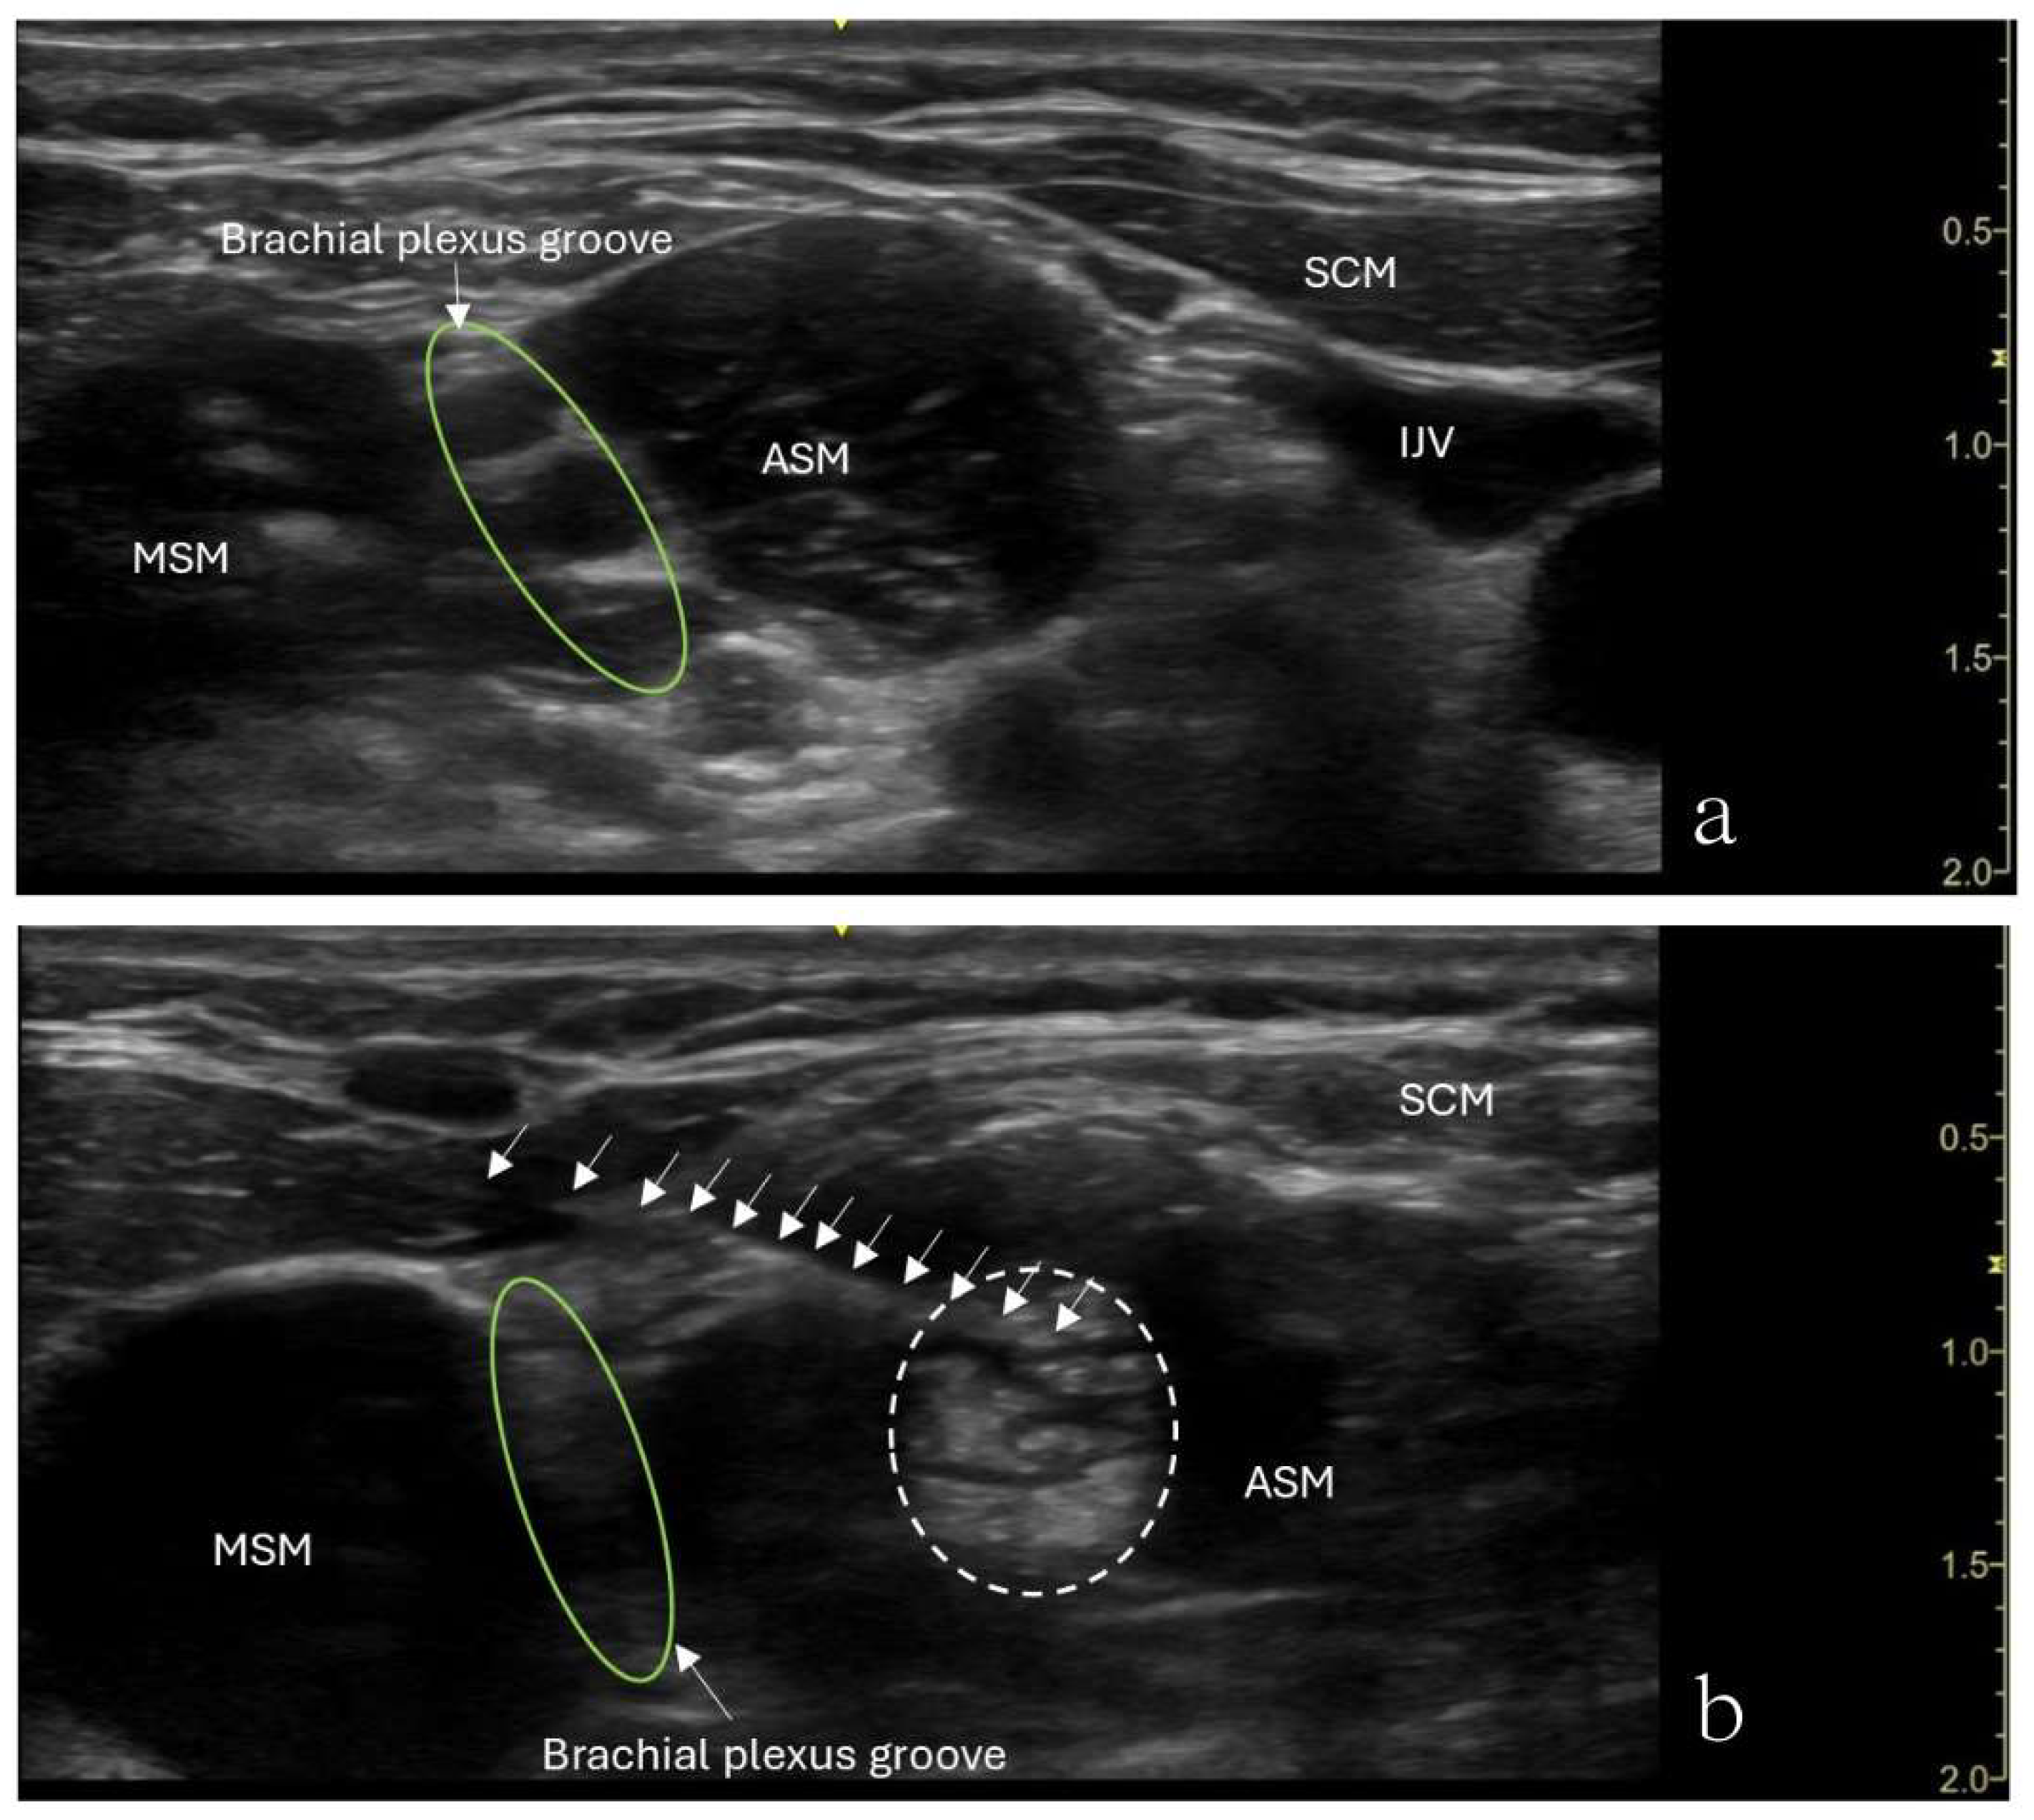

The patient underwent ultrasound-guided ASMB under minimal sedation. A high-frequency linear ultrasound probe identified the anterior scalene muscle and adjacent neurovascular structures. After sterile preparation, a 24-gauge, 40-mm Sono-TAP needle (PAJUNK®, Germany), using an in-plane approach, was advanced from the anterior aspect of the neck posteriorly and was inserted into the middle of the anterior scalene muscle (Figure 2). After negative aspiration, 5 mL of 0.5% ropivacaine was injected incrementally (Figure 2). The block provided immediate pain relief, and there was no numbness in the right upper extremity when the arm was elevated or abducted. However, the patient developed right-sided Horner’s syndrome and experienced weakness in the right shoulder, both of which resolved shortly after the procedure. Her preexisting symptoms were resolved for approximately 3 hours following the block.

Figure 2. Ultrasound image showing an anterior scalene muscle block in a 15-year-old girl. (a) The needle (arrows) in inserted into the anterior scalene muscle (ASM), and needle tip placement is in the middle of the anterior scalene muscle. The needle was advanced from the anterior aspect of the neck posteriorly. (b) Brachial plexus groove is in between the ASM and MSM. Injected local anesthetics (dashed circle) and an increased muscle size was noticed.